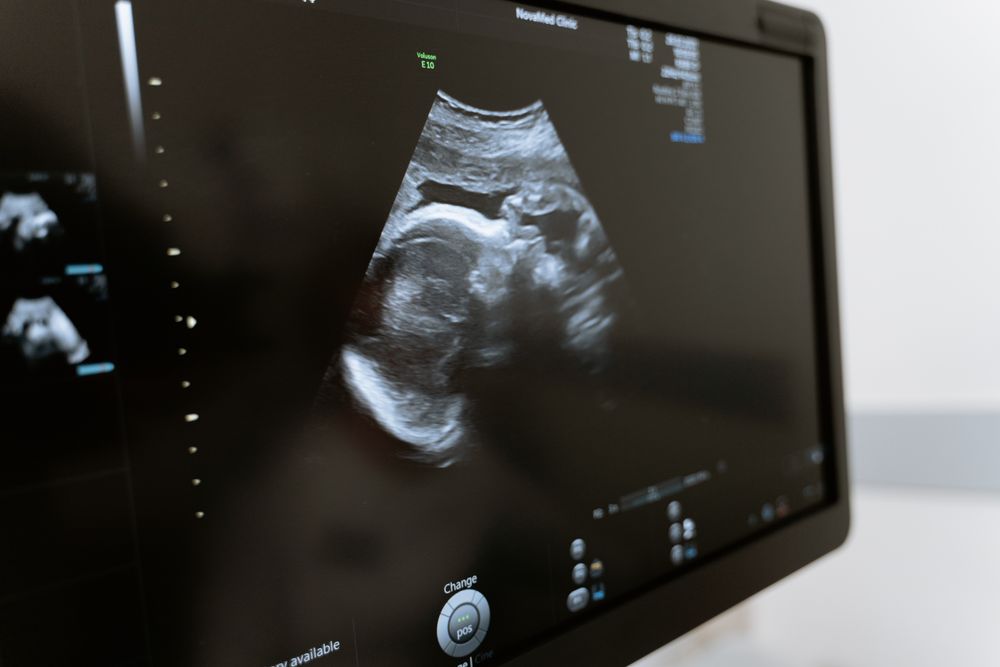

échographie De Datation à 7sa . Échographie de datation Déroulement Il est recommandé de ne pas tirer de conclusions hâtives et d'attendre quelques semaines pour réaliser une nouvelle échographie Bien que l'échographie ne soit pas infaillible, elle est fiable et procure des informations.

Source: wardfundyor.pages.dev Echographie de datation, vidéo 1 YouTube , L'échographie de datation : qu'est-ce que c'est ? L'échographie de datation est la toute première échographie réalisée durant votre grossesse L'échographie de datation à 7 SA est un examen essentiel pour diagnostiquer la santé maternelle et foetale

Échographie dite précoce ou échographie de datation Céline Foinant . Si lors d'une échographie de datation à 7SA, il n'y a pas d'embryon visible, il est important de ne pas paniquer En effet, comme son nom l'indique, l'échographie de datation permet de dater avec précision l'âge de la grossesse, et a fortiori de déterminer la date du terme avec une plus grande précision qu'avec la date des dernières règles ou de l'ovulation